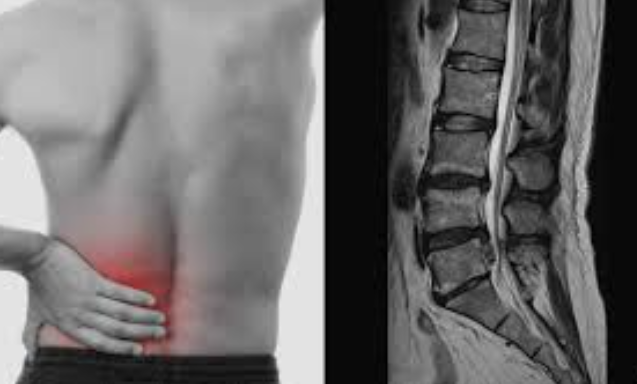

허리뼈(요추) 사이에는 디스크(추간판)라는 젤리 같은 구조물이 있어 충격을 흡수합니다.

그런데 나이가 들거나 무리한 동작으로 이 디스크가 밀려나와 신경을 눌러 통증을 유발하는 것이 허리디스크입니다.

젊은 사람에게도 생기지만, 무거운 물건을 자주 드는 중장년층에게 특히 잘 생깁니다.